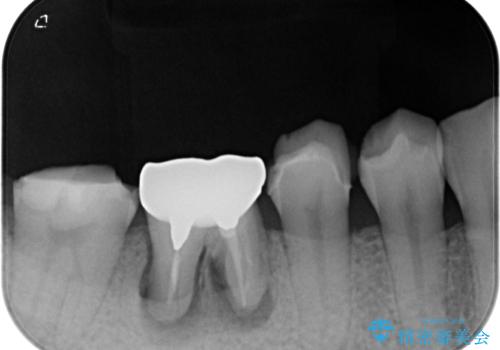

診察より、奥から2番目の歯が割れている可能性が非常に高いため、まずは奥から2番目の歯の状態を診断することとしました。

クラウンを外したところ、目視でも確認できる破折線が認められたため、抜歯することとしました。

抜歯後も膿の出口が消えず、一番奥の歯を診察したところ神経組織の反応がなかったため、根管治療を行うこととしました。